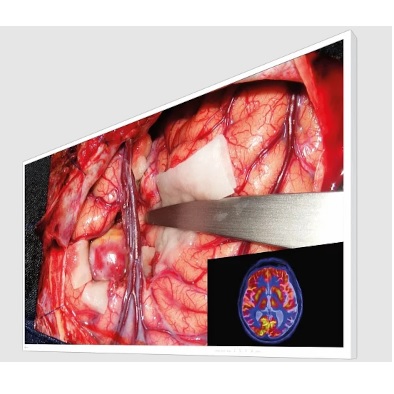

• systemy wspierające diagnostykę medyczną oraz systemy obrazowania radiologicznego